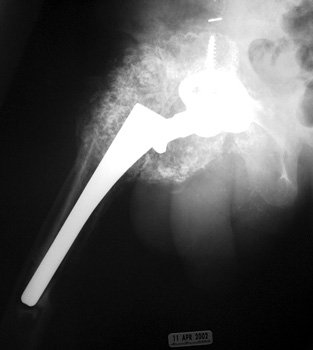

Heterotopic Bone Formation

May be associated with pain and loss of range of motion.

HETEROTOPIC BONE FORMATION—Fusing greater trochanter to lateral acetabulum

HETEROTOPIC BONE FORMATION adjacent to loose femoral component, plain film and CT